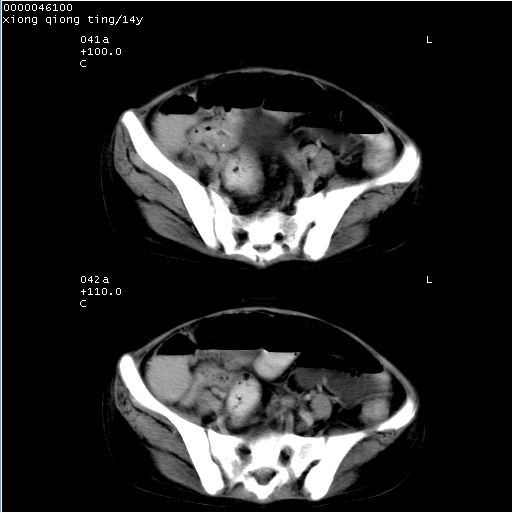

中下腹及盆腔ct轴位平扫+增强扫描(层厚10mm,螺距1.0,重建间隔10mm),图像如下:

(注:患儿检查当日上午9时口服胃肠道对比剂,下午3时许行ct扫描检查,未行对比剂直肠保留灌肠,检查当日患儿腹泻)

中下腹及盆腔ct轴位扫描(ps+ce)提示:腹部肠管明显充气扩张,并见数个不同宽度之气液平面;疑不全性肠梗阻或肠郁张。临床会诊考虑为患儿腹泻,肠郁张所致;后来未经特殊处理,患儿大便恢复正常,亦无腹胀。